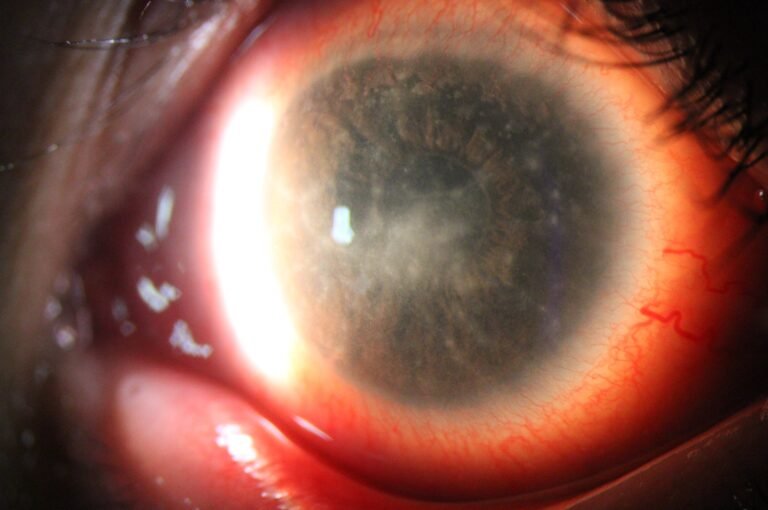

Dry Eye

Full ocular surface analysis

Advanced Dry Eye analysis

Built-in Digital Analysis